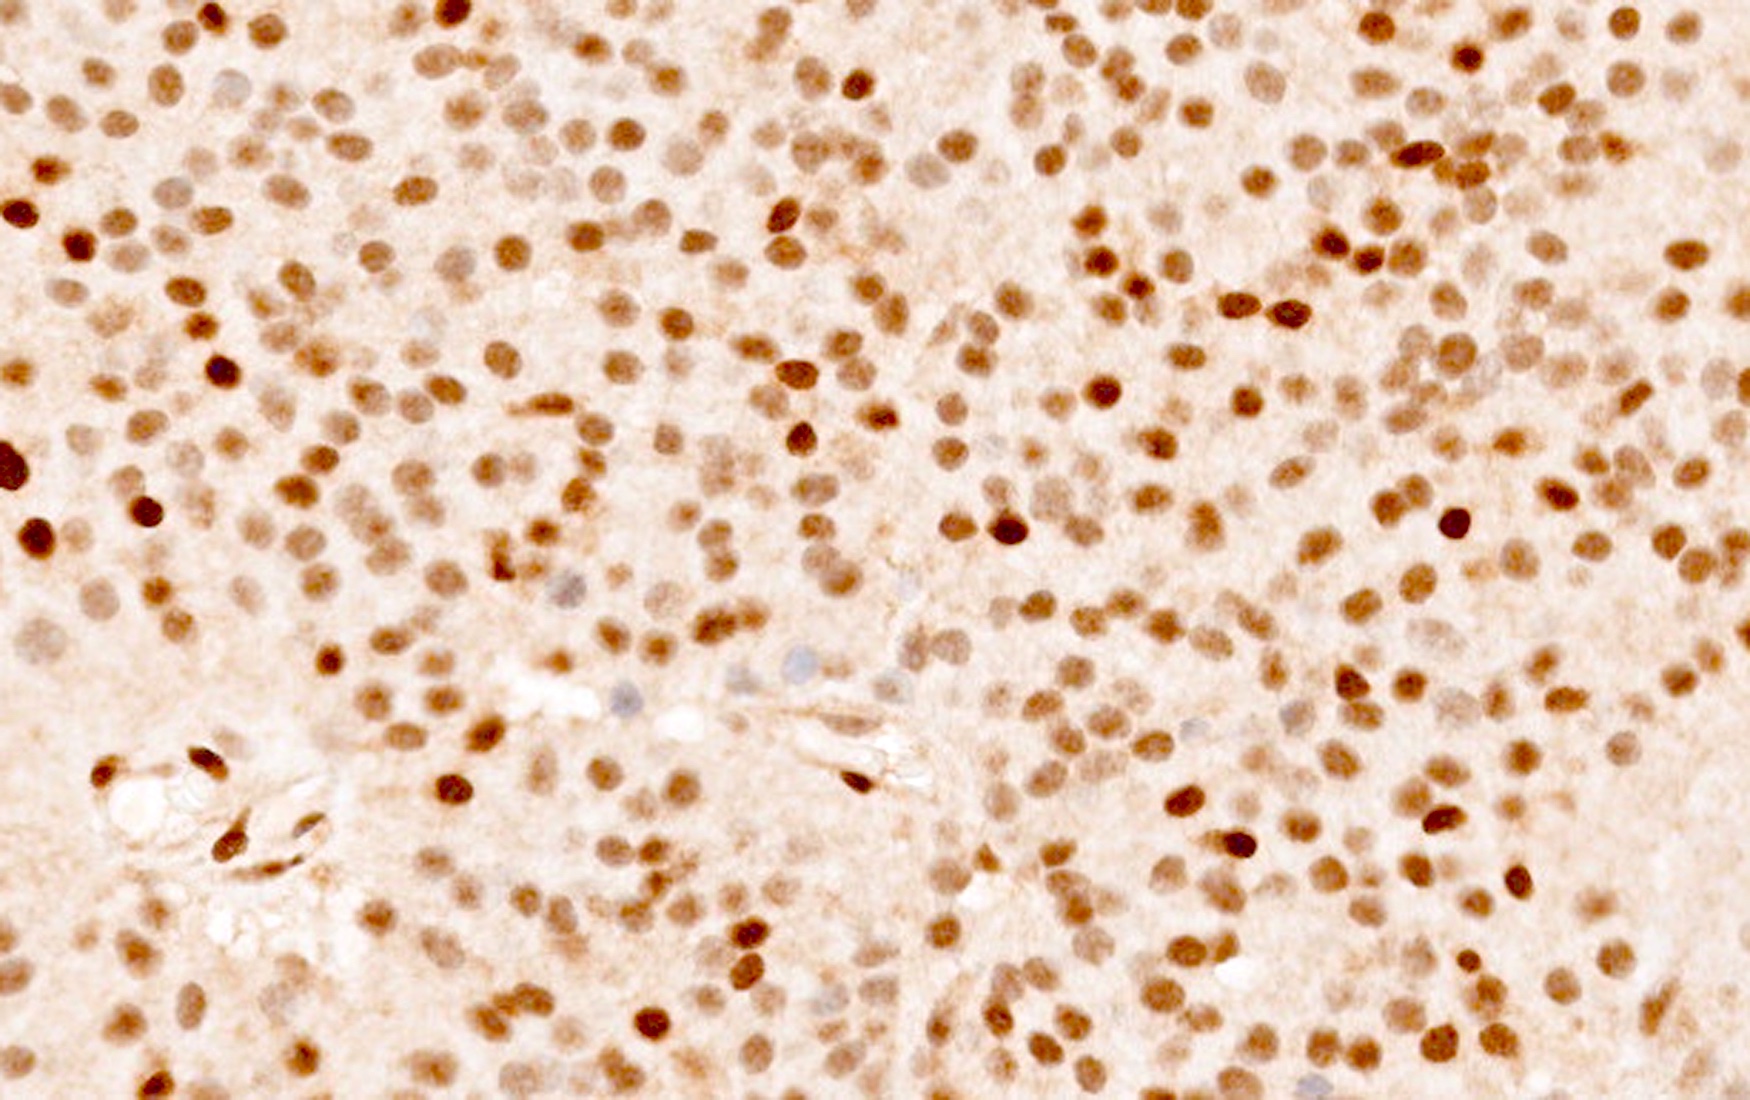

Microscopic (histologic) images

Contributed by Sylvia L. Asa, M.D., Ph.D.

Positive stains

- Stains for pituitary transcription factors (Pit1, Tpit, SF1, ER and GATA3) and hormones provide the basis for tumor classification (see Diagrams / tables)

- Paranuclear CAM 5.2 positive fibrous bodies are a conspicuous feature present in > 70% of tumor cells of sparsely granulated somatotroph tumors

- Ki67 immunolabeling often used to characterize tumors with elevated proliferative indices